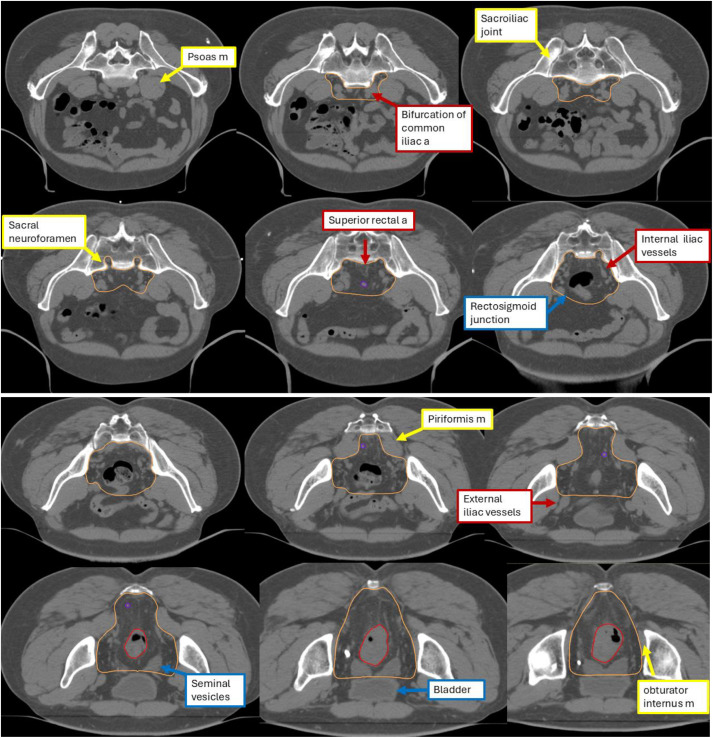

Thể tích bia dự phòng phía trên (Trên chỗ nối trực tràng–đại tràng sigma)

Để bao phủ nhóm hạch chậu trong, thể tích bia dự phòng bắt đầu từ mức chia đôi của động mạch chậu gốc thành động mạch chậu ngoài và chậu trong. Sử dụng biên 0,7 cm xung quanh các mạch chậu trong, đồng thời loại bỏ các phần xương và cơ không bị xâm lấn. Để bao phủ nhóm hạch trước xương cùng, contour được mở rộng 1 cm ra phía trước xương cùng, phía trên mức của mạc treo trực tràng, nhằm đảm bảo bao phủ đầy đủ vùng trước xương cùng; mở rộng ra hai bên tới khớp cùng–chậu, và ra phía sau vào các lỗ cùng, nơi thông với khoang trước xương cùng, do tái phát theo đường quanh thần kinh dọc theo rễ thần kinh cùng rất khó điều trị cứu vãn.

Thể tích bia dự phòng đoạn giữa (Ở ngang mức mạc treo trực tràng và bàng quang)

Để tiếp tục bao phủ nhóm hạch chậu trong, contour được mở rộng ra phía trước tới mặt sau của các mạch chậu ngoài, với biên ít nhất 7 mm xung quanh các mạch chậu trong. Đối với bao phủ nhóm hạch bịt, chúng tôi bao gồm một dải rộng 1 cm dọc theo các cơ bịt trong. Bắt đầu từ chỗ nối trực tràng–đại tràng sigma, contour mở rộng ít nhất 1 cm ra phía trước từ mạc treo trực tràng để bao phủ các hạch mạc treo trực tràng. Biên 1 cm xung quanh cân của mạc treo trực tràng nhằm bù trừ cho sự thay đổi hàng ngày về phân/khí và có thể mở rộng vào các cơ quan vùng chậu phía trước để tính đến sự thay đổi vị trí bàng quang hàng ngày.

Thể tích bia dự phòng phía dưới (Dưới mức bàng quang)

Bao phủ nhóm hạch bịt tiếp tục xuống đến ngang mức ống bịt. Bao phủ mạc treo trực tràng được kéo dài xuống thêm 2 cm về phía dưới từ cực dưới khối u trực tràng hoặc đến mức sàn chậu, tùy theo mức nào thấp hơn. Đối với các khối u trực tràng trung bình đến cao, việc loại trừ ống hậu môn khỏi thể tích bia có thể làm giảm nguy cơ hội chứng sau cắt trước thấp và tình trạng đại tiện không tự chủ. Trong trường hợp không có xâm lấn đại thể vào hố ngồi–trực tràng hoặc cơ nâng hậu môn, bờ bên của thể tích bia không cần mở rộng vượt quá các cơ nâng hậu môn.